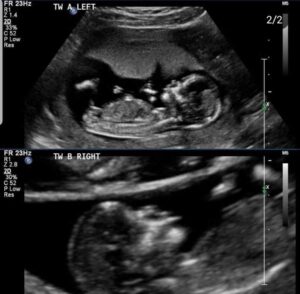

We booked in our dating scan and joked that there was going to be two. Sure enough, there they were! Two little-flashing heartbeats. I couldn’t have been more proud or excited. My husband and I both looked and each other and laughed. Time to get a van!

We booked our second scan at 14 weeks. A friend of mine told us to ask the sonographer if they could tell the sex, so I thought I’d be cheeky and ask just in case. I’m so impatient and hate surprises! We showed up to our scan and I was delighted and relieved to see our two babies were both alive and dancing around on the screen! Our Sonographer told us they were the healthiest twins she had ever scanned! They were both growing beautifully and they were pretty much the exact same size as each other. She also told us they were two little boys! As you can imagine, the excitement was unreal. Two boys to complete our little family! How lucky were we! Two healthy babies growing so perfectly.